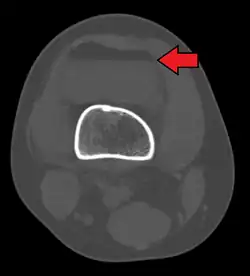

Hemartrose é um sangramento dentro do espaço articular. Se não houver fratura mandibular, poderá haver presença de um edema moderado, dor na área da articulação temporomandibular (ATM), dor ao movimento e mobilidade reduzida.[1][2][3]